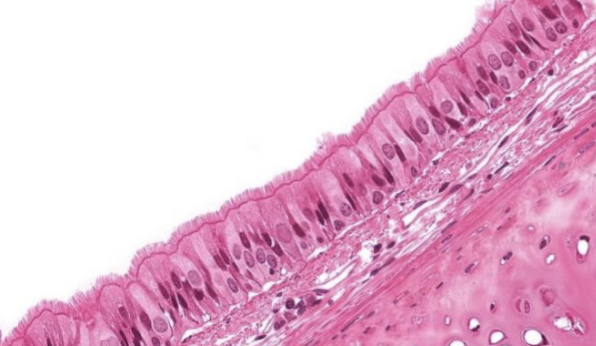

Indique tipo de tejido epitelial

pseudoestratificado